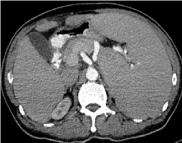

Abdominal Ultrasonography demonstrated a markedly enlarged spleen of 22.9 cm and a small 0.5 cm gall bladder polyp. Contrast Enhanced Computed Tomography (CECT) of the neck, thorax, abdomen and pelvis, apart from massive splenomegaly, (Figure 4) revealed no adenopathy except for minimally enlarged para aortic lymph nodes with largest measuring 1.3 × 1.1 cm at the level of L3/L4 intervertebral disc and an enlarged prostate of 3.7 × 5.1 × 3.2 cm. Hepatitis B core antibody was reactive with undetectable HBS antigen and Hepatitis C antibody. Serum protein electrophoresis demonstrated reduced alpha 2 globulins, no paraproteins, and elevated free kappa light chains. Free serum Kappa was 82.08 mg/L (normal range 3.30-19.40), Free Lambda 32.98 mg/L (normal range: 5.71-26.3) and ratio of Kappa/Lambda high at 2.488. MYD88 p. Leu265Pro mutation was negative.

Figure 4. CT abdomen showing spleen size before rituximab.

A diagnosis of autoimmune hemolytic anemia (AIHA) secondary to SMZL was made. Corticosteroids at 1 mg/kg with folate supplements were commenced and the patient was started on 6 weekly doses of rituximab at 375 mg/m2 as the patient refused splenectomy.  Because of presence of Hepatitis B core antibody and treatment with rituximab and steroids, prophylactic Tenofovir was commenced to avert a Hepatitis B flare. Splenomegaly and signs of hemolysis rapidly improved. Hemolysis abated and CBC improved rapidly (Table 1 and Figure 1) and rapid steroid taper was instituted after 2nd week of treatment.  Repeat CT abdomen in follow-up clinic revealed spleen size of 9 cm after only two rituximab injections (Figure 5).

Figure 5. CT abdomen showing reduction of spleen size after two injections of rituximab.